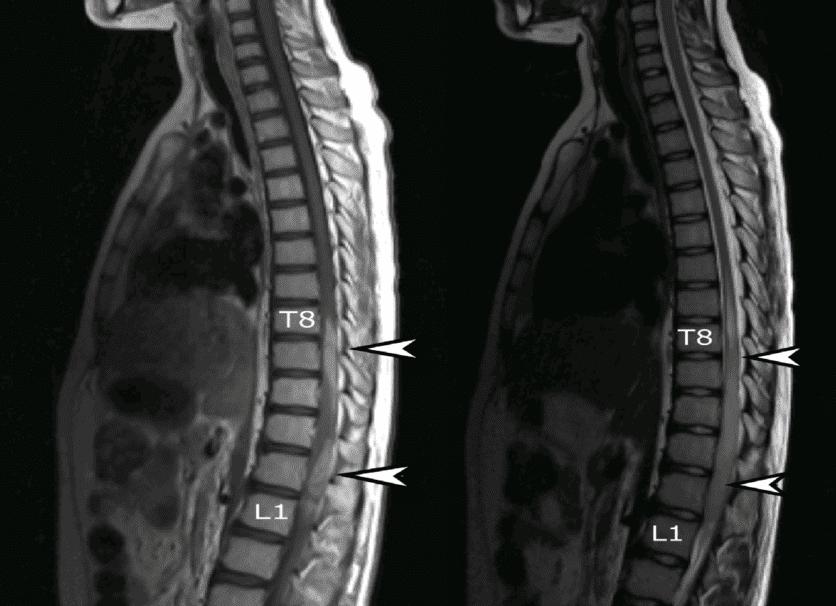

Чтобы досконально посмотреть заболевание позвоночника и выявить нарушение в области спины невролог назначает МРТ проблемного участка позвоночника. Процедура выполняется с двух проекций в области пораженного отдела позвоночника. Проекции носят названия сагиттальной и поперечной. Оптимальной толщиной среза считается толщина в 3–4 мм без учета зазоров. Поперечная проекция представлена снимком самой минимальной толщины, какой только возможно. К положению диска под углом производится срез на изображении. Для распознавания опухоли и обработки данных делают МРТ с введением контрастного вещества для просматривания деформаций дисков и выявления наличия грыж.

Для выявления заболеваний позвоночника и исследования спинного мозга врач-невролог назначает МРТ пояснично-крестцового отдела позвоночника. Его делают обязательно в двух проекциях на уровне поражения: поперечной и сагиттальной. Наилучшей толщиной среза изображения является 3-4 мм без зазоров между ними.

В поперечной проекции делают снимок Т2 взвешенного типа с минимальной толщиной среза насколько это возможно. Срез делается под углом, соответствующим положению межпозвоночного диска.

Для дифференцирования заболевания с опухолью или мальформацией производят МРТ с введением контрастного вещества. При этом хорошо видны межпозвоночные диски и если есть – грыжи.

Для того чтобы выявить грыжу в шейном отделе, достаточно Т2- взвешенных МР-томограмм, выполненных в сагиттальной и аксиальной проекциях при стандартной толщине среза в 3 мм. МРТ шейного отдела позвоночника делают: